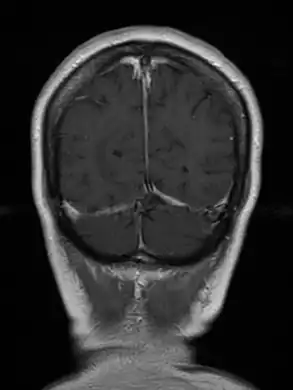

Cerebral toxoplasmosis (with primary involvement in the right occipital lobe)

Cerebral toxoplasmosis